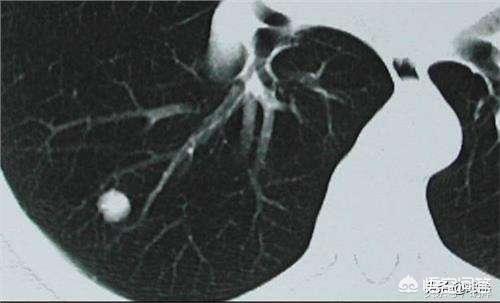

Lungenknoten werden je nach ihrer Dichte in verschiedene Typen eingeteilt: Knoten mit höherer Dichte, die auf dem CT der Brust als weiße Punkte erscheinen, werden als solide Knoten bezeichnet, während Schliffknoten eine geringere Dichte haben und wie Wasserdampf auf dem Glas aussehen. Glasschliffknötchen, insbesondere reine Glasschliffknötchen, sind in der Regel bösartiger.

In der chinesischen medizinischen Leitlinie heißt es zur Definition des Lungenknotens: Die Bildgebung (Thorax-CT) zeigt einen fokalen, rundlichen, festen oder subsoliden Lungenschatten mit einer erhöhten Dichte und einem Durchmesser von ≤3 cm, der isoliert oder mehrfach vorhanden sein kann und nicht von einer pulmonalen Atelektase, einer Vergrößerung der hilären Lymphknoten und einem Pleuraerguss begleitet ist.

Im Allgemeinen wird jeder Schatten mit erhöhter Dichte in der Lunge mit einem Durchmesser von weniger als 3 cm als Lungenknoten bezeichnet, und der Grad des Risikos hängt nicht nur von der Größe ab, sondern muss auch in Verbindung mit der Morphologie, der Dichte und der Geschwindigkeit der Vermehrung des Knotens bestimmt werden.

Wir kennen diese Vorstellung von der Diagnose der Krankheit, und dann gehen wir zurück zum Kopf, um über Lungenknoten zu sprechen. Lungenknoten sind runde oder unregelmäßige Läsionen mit einem Durchmesser von höchstens 3 cm in der Lunge, die in der Bildgebung als Schatten mit erhöhter Dichte erscheinen, die homogen oder inhomogen sein können, die einzeln oder mehrfach vorkommen können und die klare oder unklare Grenzen haben können.